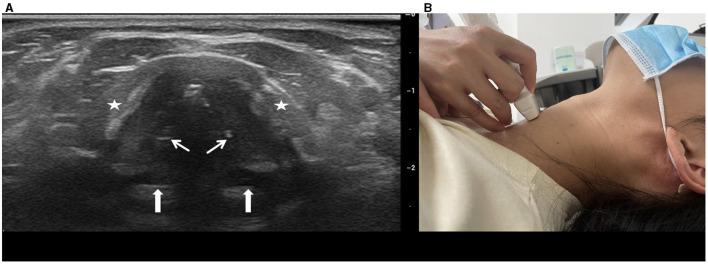

This study aimed to analysis the cervical tracheal characteristics of obstructive sleep apnoea-hypopnoea syndrome (OSAHS) patients using ultrasound.

One hundred and thirteen patients with OSAHS and 113 age-, sex-, height-, weight-, and BMI-matched healthy controls underwent cervical tracheal sonographic examination. Tracheal wall motion was monitored and sonographic measurements of the airway lumen were obtained during quiet respiration, deep respiration, and the Müller maneuver. Tracheal displacement during the Müller maneuver was monitored and quantified. Measurements were compared between groups.

方法

113例OSAHS患者和113例年龄、性别、身高、体重和BMI匹配的健康对照者接受颈段气管超声检查。在静息呼吸、深呼吸和Müller动作期间监测气管壁运动,并获取气道腔的超声测量值。监测并量化Müller动作期间的气管移位。比较两组间的测量值。